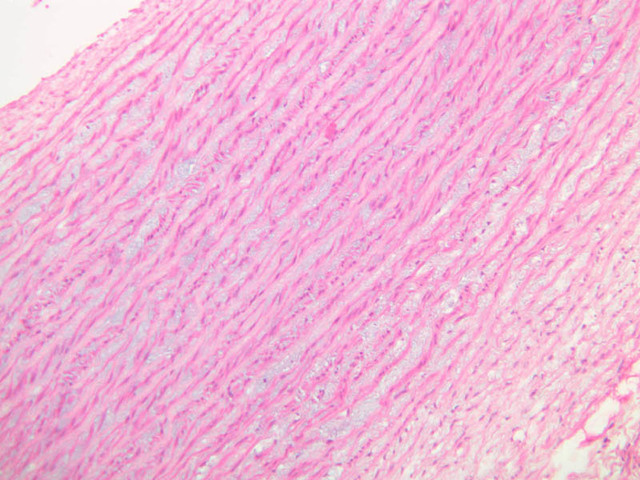

The blood is pumped from the heart into large, elastic (conduction) arteries. Examine a section of the aorta (A-26, H&E [2.5x, 10x, 20x, 40x-labeled] [2.5x, 10x-labeled, 20x, 40x]) which is a typical elastic artery. Although the tunica intima and tunica media are difficult to distinguish, note that together they are much thicker than the tunica adventitia. Using high power magnification, examine the tunica media and identify the cell types and fibers, recalling that elastic tissue appears light pink and refractive in H&E preparations. Compare this slide with a section of aorta stained to demonstrate elastic fibers (A-27, verhoeff [2.5x, 10x, 20x, 40x-labeled] [2.5x, 10x]).

Note how extensive the elastic tissue is in the tunica media. The elastic tissue is arranged in the form of numerous concentric elastic lamellae, which are cross connected by slender elastic fibers. Observe the distribution of elastic fibers in the tunica intima (A- 27 [2.5x, 10x, 20x, 40x]) and tunica adventitia (A-27 [10x, 20x, 40x]). The internal and external elastic membranes are not well demarcated in the aorta since so many elastic lamellae are present. The elasticity of the aorta allows it to expand and absorb much of the pressure during contraction of the left ventricle (i.e., systole). When the ventricle relaxes (diastole), the elastic aorta contracts, continuing the movement of blood into the medium and muscular arteries.